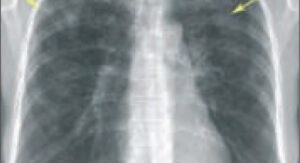

Альвеолит — заболевание, связанное с диффузным воспалением альвеол (самых маленьких альвеол — конца дыхательных путей) и постепенным разрастанием соединительной ткани. Из-за нарушений строения легких нарушается газообмен и формируется соответствующая клиническая картина. Общая информация Заболевание делится на несколько видов с разной клинической картиной. Соответственно, объем исследования и схемы лечения различаются. Альвеолит может быть вторичным, т.е. сопровождать …